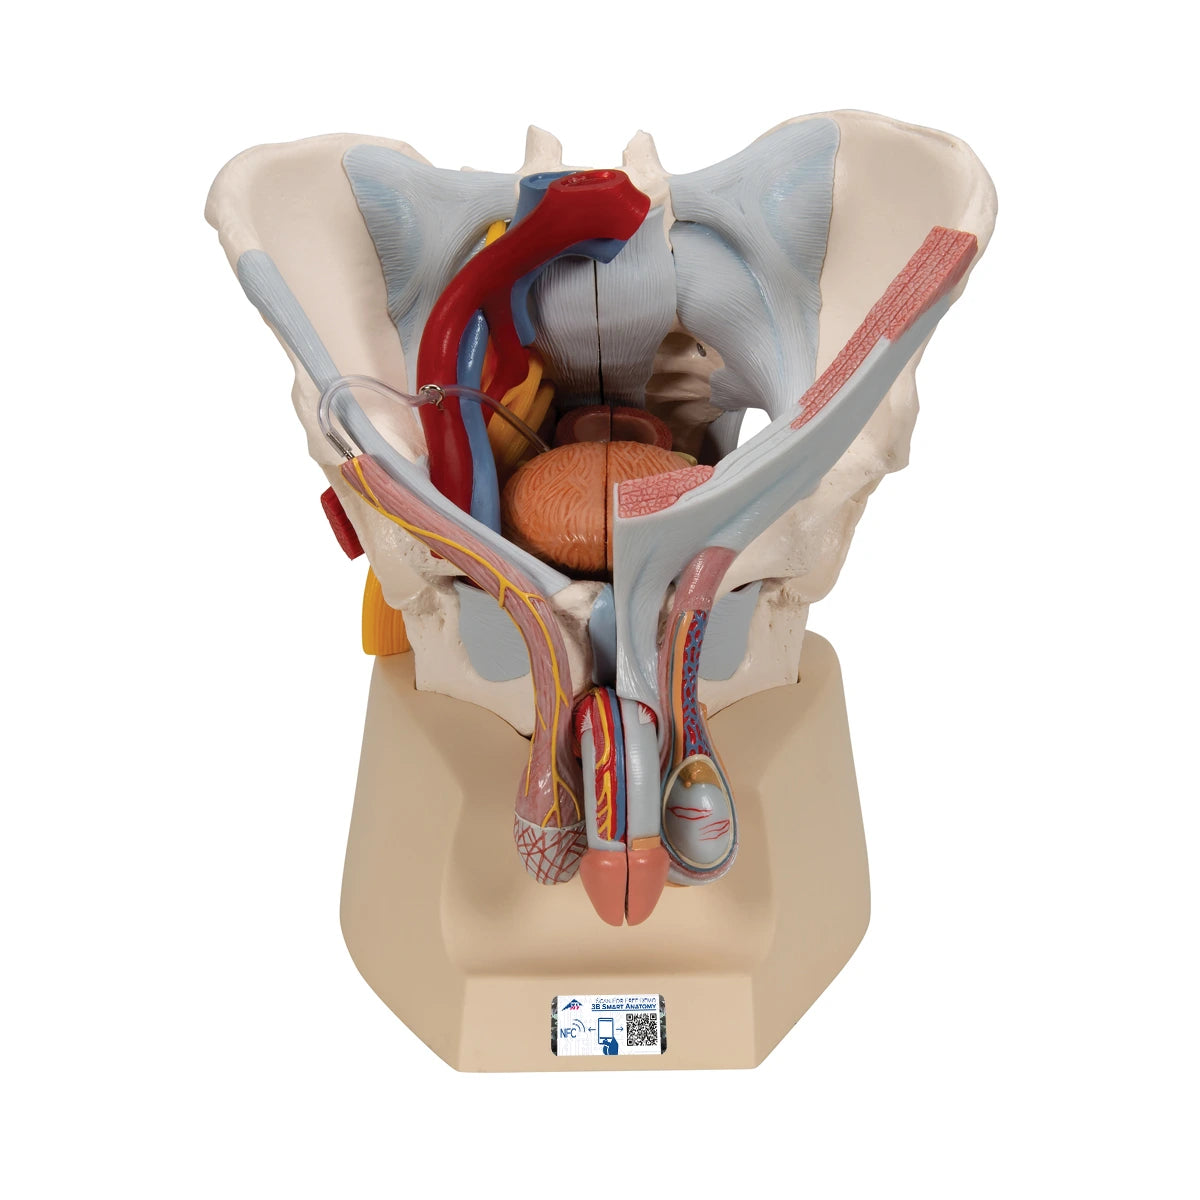

3B Scientific

Pelvis masculina con ligamentos, vasos, nervios, suelo pélvico y órganos 7 piezas

Precio de venta$31,138.04